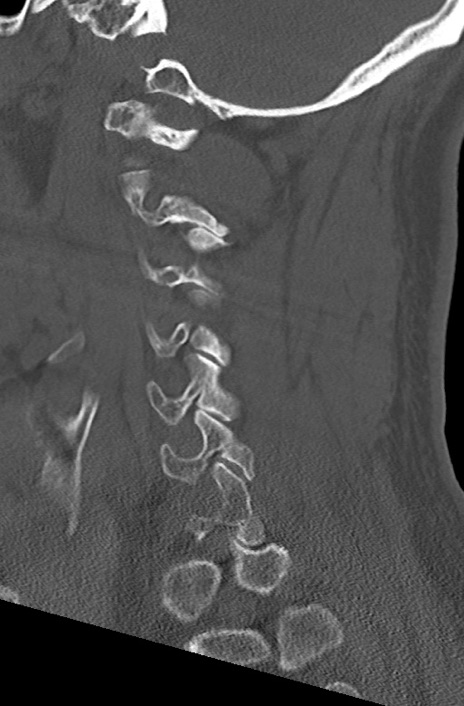

頚椎CT

矢状断像と横断像